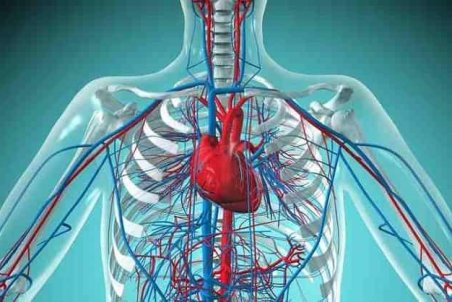

خوراکیهایی که رگهای بدن را پاکسازی میکند

پاکسازی رگهای بدن برای پیشگیری از بروز سکتههای مغزی و قلبی مهم و ضروری است که با رعایت چند نکته ساده میتوان رگها را پاکسازی کرد.

خوراکیهای شگفتانگیز برای پاکسازی رگهای بدن

با توجه به اهمیت زیاد حفظ سلامت رگها، مجموعهای از خوراکیهای شگفتانگیز که برای پاکسازی رگهای بدن مفید هستند را معرفی کردهایم.